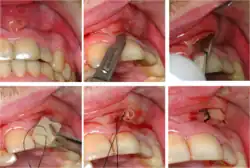

Gutta-percha point indicating abscess origin